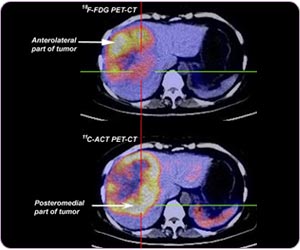

11C標記醋酸和18F標記葡萄糖在同一肝細胞癌病灶不同部位分別呈現出高代謝,兩者存在互補關系。